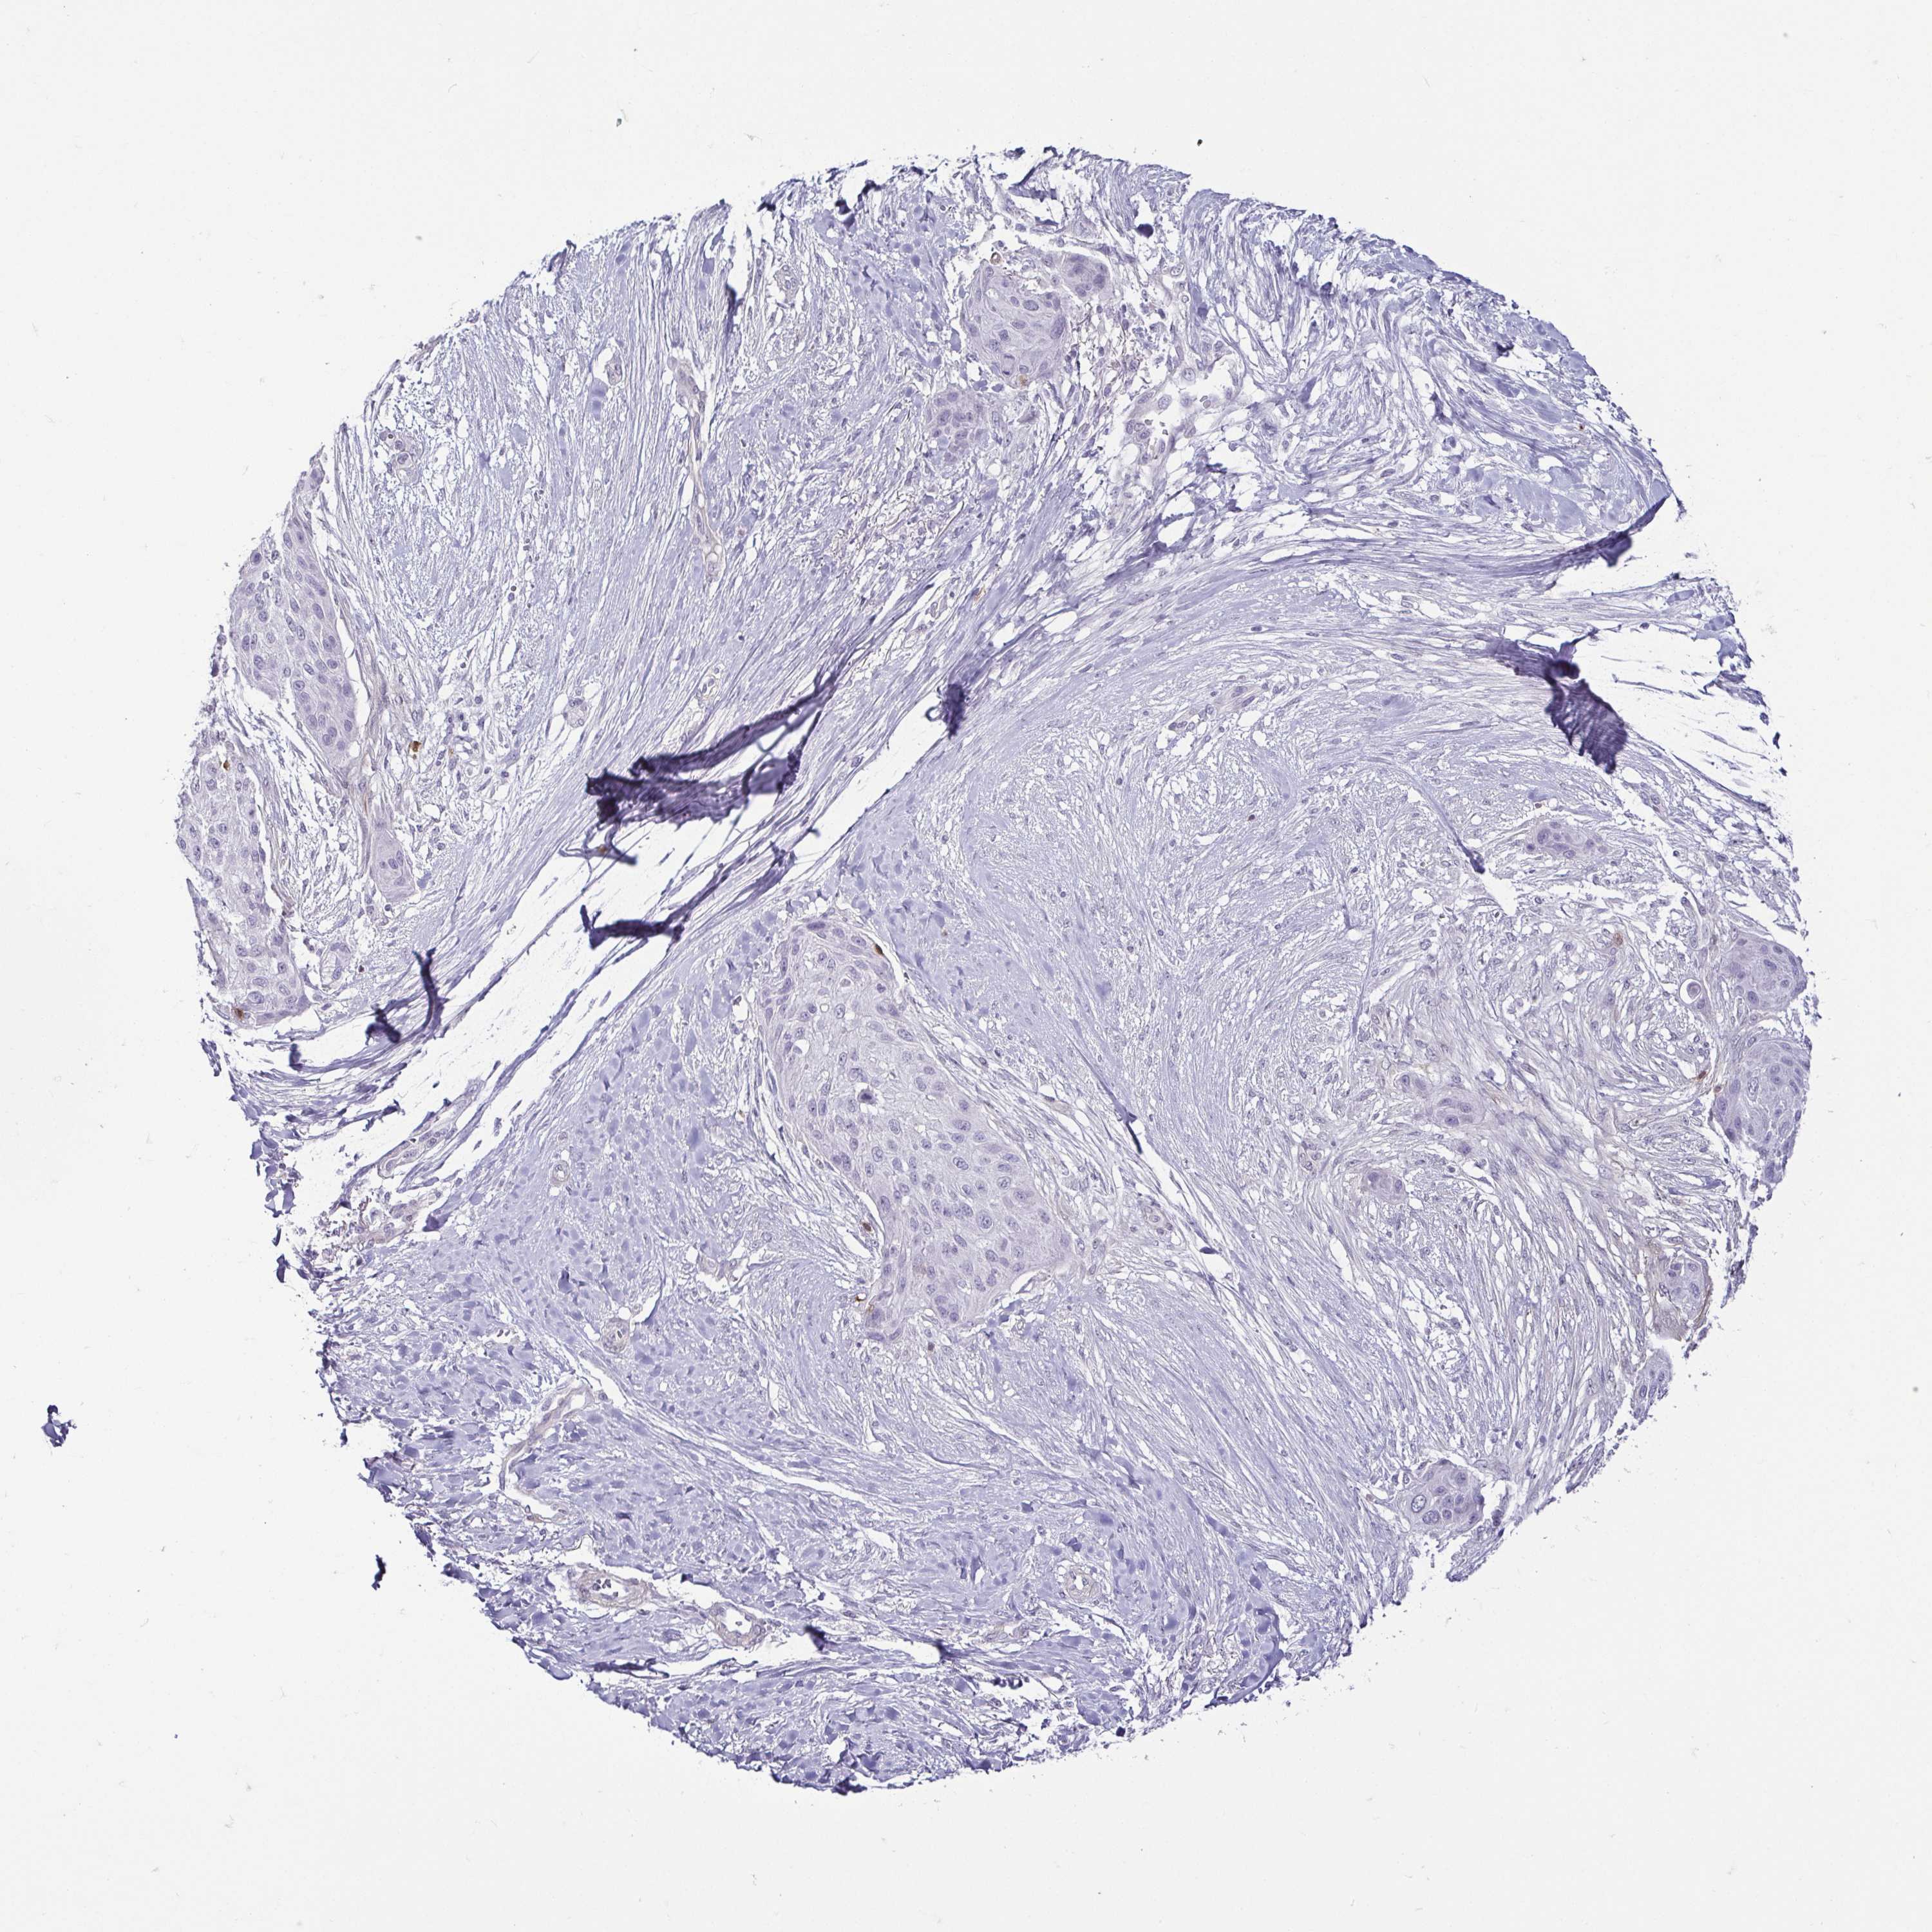

Basal cell and squamous cell cancer

SKIN CANCER - Protein expressioni

A mouse-over function shows sample information and annotation data. Click on an image to view it in a full screen mode. Samples can be filtered based on level of antibody staining by selecting one or several of the following categories: high, medium, low and not detected. The assay and annotation is described here.

Antibody stainingi

Antibody staining in the annotated cell types in the current human tissue is reported as not detected, low, medium, or high, based on conventional immunohistochemistry profiling in selected tissues. This score is based on the combination of the staining intensity and fraction of stained cells.

Each image is clickable and will lead to virtual microscopy that enables deeper exploration of all samples and also displays staining intensity scores, fraction scores and subcellular localization as well as patient and tissue information for each sample.

Antibody HPA030180

Antibody CAB018632

Staining

High

Medium

Low

Not detected

Intensity

Strong

Moderate

Weak

Negative

Quantity

>75%

75%-25%

<25%

None

Location

Nuclear

Cytoplasmic/membranous

Cytoplasmic/membranous,nuclear

Basal cell carcinoma

Squamous cell carcinoma, NOS